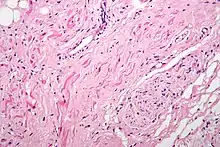

Гистология

Атипичные мышечные волокна сердца — это специализированные проводящие кардиомиоциты, богато иннервированные, с небольшим количеством миофибрилл и обилием саркоплазмы[B: 5].

Синусовый узел

Клетки, составляющие синусовый узел, гистологически отличаются от клеток рабочего миокарда. Хорошим ориентиром служит выраженная a.nodalis (узловая артерия). Клетки синусового узла по размерам меньше клеток рабочего миокарда предсердия. Они группируются в виде пучков, при этом вся сеть клеток погружена в развитый матрикс. На границе синусового узла, обращенной к миокарду устья верхней полой вены, определяется переходная зона, которая может расцениваться как присутствие клеток рабочего миокарда предсердий в пределах синусового узла. Такие участки вклинения клеток предсердия в ткань узла чаще всего встречаются на границе узла и пограничного гребня (выступа стенки правого предсердия сердца, которым заканчиваются вверху гребенчатые мышцы)[2].

Гистологически синусовый узел состоит из т.н. типичных клеток узла. Они располагаются беспорядочно, имеют веретенообразную форму, а иногда разветвления. Для этих клеток характерно слабое развитие сократительного аппарата, случайное распределение митохондрий. Саркоплазматический ретикулум развит хуже, чем в миокарде предсердий, а система T-трубочек отсутствует. Это отсутствие, правда, не является критерием, по которому выделяются "специализированные клетки": часто система T-трубочек отсутствует и в рабочих кардиомиоцитах предсердия.

По краям синусового узла наблюдаются переходные клетки, отличающиеся от типичных лучшей ориентацией миофибрилл наряду с более высоким процентом межклеточных соединений - нексусов. Находимые ранее "вставочные светлые клетки", по последним данным, являются не более чем артефактом.

Область атриовентрикулярного соединения

С точки зрения гистологии, клетки предсердного компонента АВ-соединения мельче, чем клетки рабочего миокарда предсердий. Клетки переходной зоны имеют вытянутую форму и иногда разделены тяжами фиброзной ткани. В компактной зоне АВ-узла клетки расположены более тесно и часто организованы во взаимосвязанные пучки и завитки. Во многих случаях выявляется разделение компактной зоны на глубокий и поверхностный слои. Дополнительным покрытием служит слой переходных клеток, придающий узлу трехслойность. По мере перехода узла в проникающую часть пучка наблюдается увеличение размеров клеток, но в основном клеточная архитектоника сравнима с таковой в компактной зоне узла. Границу между АВ-узлом и проникающей частью одноименного пучка трудно определить под микроскопом, поэтому предпочтительней чисто анатомическое разделение в районе точки входа оси в фиброзное тело. Клетки, составляющие ветвящуюся часть пучка, по своим размерам напоминают клетки миокарда желудочков.

Клетки левой ножки пучка Гиса можно отличить от клеток рабочего миокарда по их расположению и характеристиках при окрашивании[2].

Идентификация терминальных разветвлений в дистальных отделах обеих ножек пучка Гиса затруднена ввиду их цитологического сходства с обычным миокардом[2].

Волокна Пуркинье

Бледные или набухшие клетки (так называемые клетки Пуркинье) редко встречаются в миокарде предсердий и специализированной области атриовентрикулярного соединения у младенцев и детей младшего возраста; по мнению некоторых авторов являются там артефактами[2].

Клетки Пуркинье самые крупные не только в проводящей системе, но и во всём миокарде[B: 10]. Клетки Пуркинье в желудочках располагаются под эндокардом, объединяются в «волокна», по морфологии — круглые, светлые, овальной формы, без поперечной исчерченности; являясь одним из видов атипичных кардиомиоцитов, они практически не способны к сокращениям (из-за отсутствия или низкого содержания миофибрилл, Т-трубочек и митохондрий)[B: 11].

Благодаря обилию гликогена проводящие миоциты сердца отчётливо выделяются окраской гликогена кармином по методу Беста[B: 10]. При окраске азановым методом «волокна» (клетки) Пуркинье приобретают голубовато-розовый цвет[B: 11].